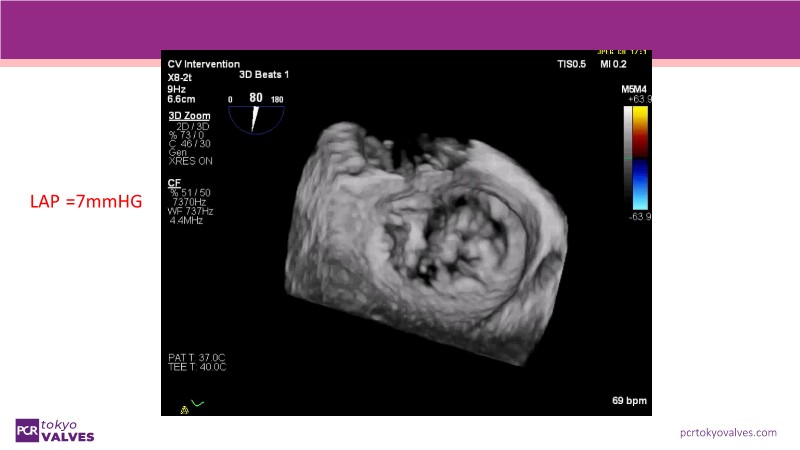

Explore the latest advancements in TEER therapy with this PCR Tokyo Valves 2025 session dedicated to MitraClip. Through expert-led case discussions, gain a deeper understanding of complex scenarios, including restricted posterior leaflet in functional mitral regurgitation, commissure lesion (A3P3), and MitraClip combined with Amulet.